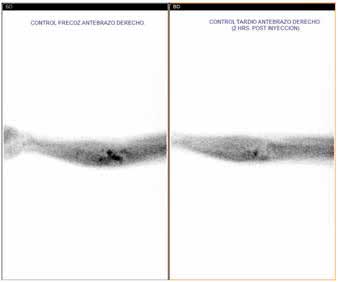

Nueve años después, presentó ascenso progresivo y persistente de iPTH refractario a terapia con dieta baja en fósforo, optimización de la diálisis, calcimiméticos (cinacalcet) y calcitriol. El cintigrama MIBI SPECT/CT® reveló un implante hiperfuncionante (Figura 1). Por lo anterior, se indicó PTX del injerto.

Figura 1: Cintigrama SESTAMIBI® implantes paratiroides de antebrazo. Exámenes preoperatorios: calcemia 8.6 mg/dL, fosfatemia 7.3 mg/dL, fosfatasas alcalinas 1115 UI/L (VN <100), iPTH 3509 pg/ml, bicarbonato plasmático 20.8 mEq/L y kalemia 4.8 mEq/L.